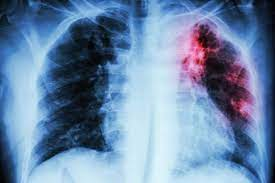

La IA mejora el cribado del cáncer de pulmón

La inteligencia artificial (IA) está transformando el cribado del cáncer de pulmón, una enfermedad con una alta tasa de mortalidad debido a la detección tardía. Las técnicas de IA pueden mejorar la precisión, la eficiencia y la accesibilidad del cribado, lo que lleva a un diagnóstico más temprano y mejores resultados para los pacientes.

👉Detección temprana: La IA puede analizar imágenes de radiografías de tórax y tomografías computarizadas (TC) con mayor precisión que el ojo humano, detectando nódulos pulmonares sospechosos en etapas más tempranas.